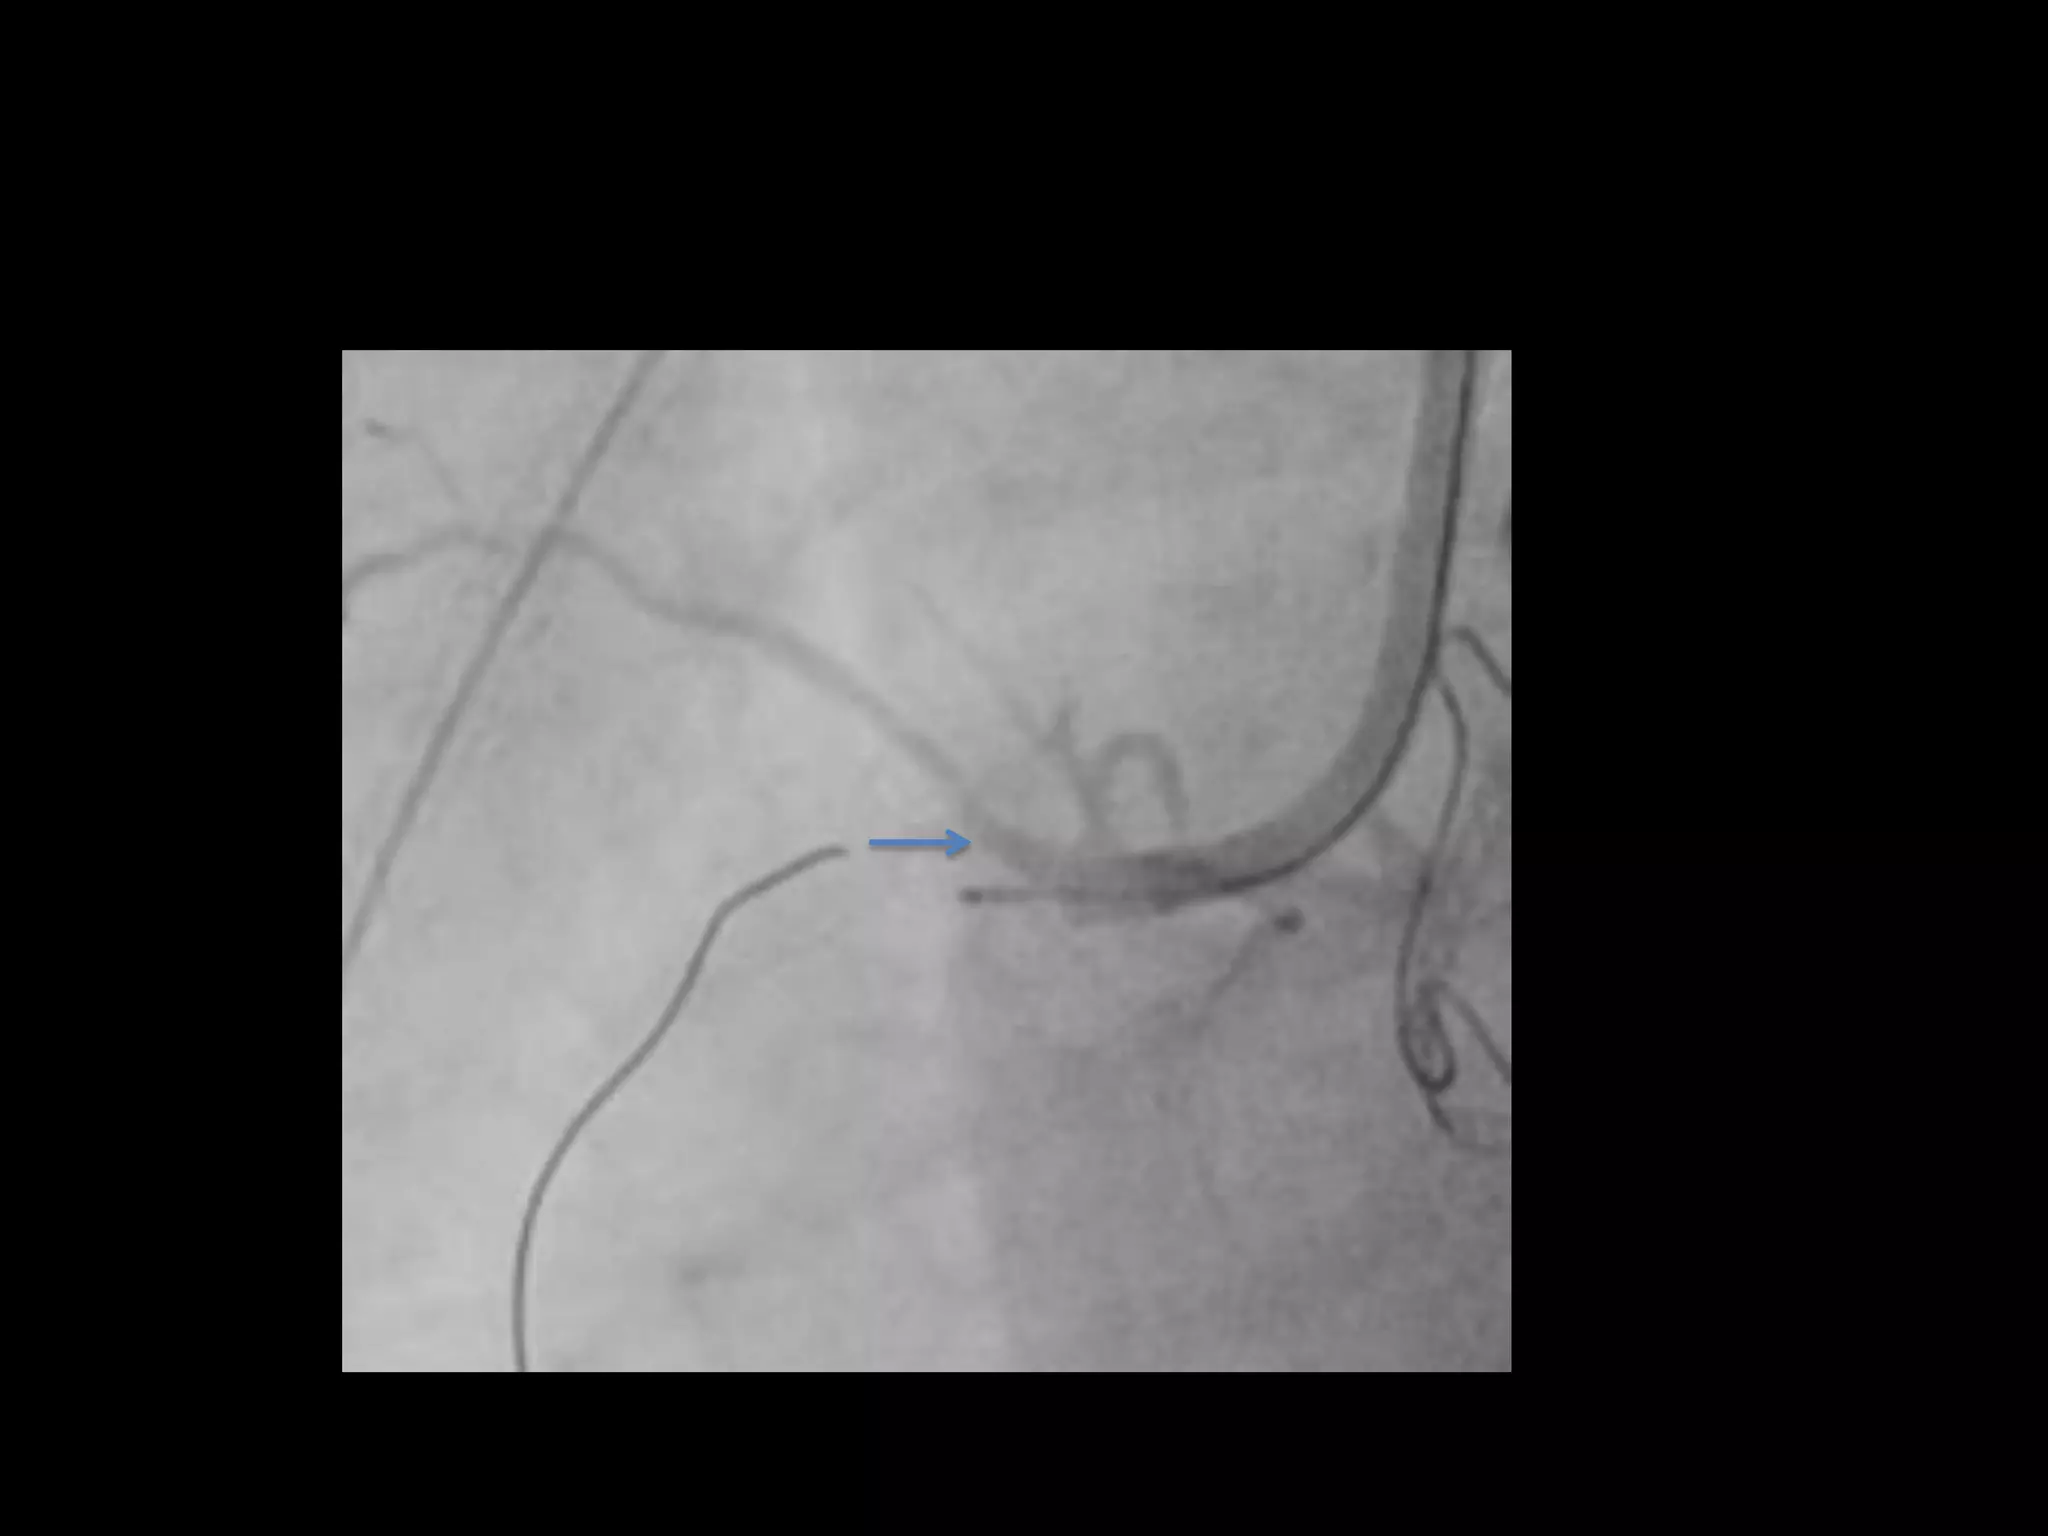

This document provides guidance on evaluating the feasibility of percutaneous coronary intervention (PCI) for a chronic total occlusion (CTO). Key factors to consider include: the patient's tolerance for a long procedure, contrast load, and radiation exposure; the CTO's proximal cap ambiguity, length, distal landing zone, and presence of interventional collaterals; and ensuring good quality angiography. With adequate planning and use of appropriate CTO techniques, feasibility is nearly always present for symptomatic patients. Success rates of CTO-PCI are reported to be 94% when using a planned approach.